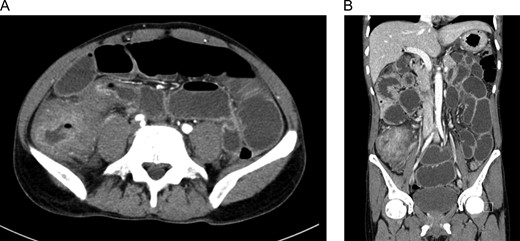

Patient was admitted for investigation. Abdomen and pelvis enhanced CT were performed revealing a swollen and edematous colon, small bowel dilatation mainly at ilial loops down to the level of the terminal ileum and cecum as there was inflammatory wall thinning and narrowing of the lumen, with normal remaining parts of colon (Fig. 1). Also, there were enlarged lymph nodes adjacent to the cecum and ileocecal junction with mild free fluid. For serology, the TB tuberculin test, HIV serology, stool analysis and upper endoscopy showed lower esophagitis, narrow inflamed pylorus and bulb of duodenum deformed with inflamed edematous mucosa with sessile polyp (biopsies were taken). Lower endoscopy showed inflamed edematous mucosa obstructing the lumen of the cecum (multiple biopsies were taken from cecum as well). Histopathology for upper endoscopy was unremarkable but biopsies from the colonic mass showed chronic unspecific inflammation with focal surface ulceration with lymphocytic infiltrate, mild edema in lamina propria and evidence of specific infection, granulomatous formation, and crypt abscess.

(A) and (B) Abdomen CT with IV and oral contrast showed small bowel obstruction secondary to cecal mass.